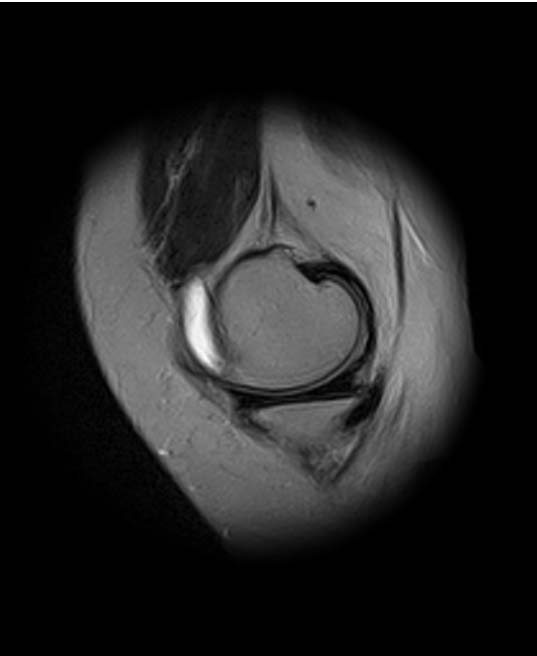

[Ortho] Показания для артроскопии

1. травма 5 лет назад - "ударилась коленом", с тех пор боли в суставе

3. стандартные рентгенограммы с небольшими изменениями - сужение

медиальной суставной щели

4. вес пациентки 80 кг, рост 165

5. сустав клинически стабилен